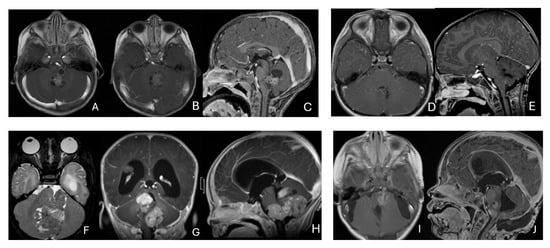

Objectives: Atypical teratoid/rhabdoid tumors (ATRTs) are rare, malignant central nervous system (CNS) neoplasms that predominantly affect infants and young children. While ATRT arises throughout the CNS, its extracranial counterpart, malignant rhabdoid tumor, occurs in other organs. A single-institutional cohort is reviewed to map anatomic distribution of pediatric ATRTs and to integrate a literature review to contextualize ATRT histogenesis from anatomical and embryological perspectives. Methods: A retrospective review was conducted on a cohort of 50 pediatric patients with ATRT treated over 20 years. Demographic, surgical, and neuroimaging data were correlated to define tumor location, extent, and compartmental involvement. A focused literature review synthesized molecular subclassifications and proposed cells of origin/cytogenesis. Results: Of the 50 ATRTs, 18 (36%) were infratentorial, 15 (30%) supratentorial, 11 (22%) in the pineal region, and 6 (12%) in the spinal compartment. Among infratentorial tumors, 10 were centered in the fourth ventricle, with or without extension into the cerebellopontine angle (CPA) cistern; the remainder arose in the CPA. Among ATRTs of the cerebral hemispheres, 3 showed bi-hemispheric involvement crossing the falx cerebri. ATRTs of the pineal region predominantly originated from the superior medullary velum. These topographic data were corelated with embryological and molecular information available in the literature. Conclusions: ATRTs arise across diverse neuroanatomical compartments—including intraparenchymal, intraventricular, extra-axial, and extradural sites—underscoring biological heterogeneity. Inactivation of SMARCB1 is the defining molecular event and principal oncogenic driver, although the upstream mechanisms precipitating these alterations remain incompletely resolved. Molecular subgroups—ATRT-TYR, ATRT-SHH, and ATRT-MYC—display distinct age distributions and anatomic predilections, implicating developmental context in tumor initiation. The characteristic cellular admixture of rhabdoid cells with mesenchymal and/or epithelial differentiation, together with intra- and extra-axial and occasional extradural presentations, supports a model in which at least a subset of ATRTs may originate from neural crest-derived lineages, despite little or no neural crest contribution to brain parenchyma development. Neural plate border progenitors with bipotent features represent a plausible intraparenchymal cell of origin. Definitive resolution of these origins and the mechanisms of SMARCB1 disruption will require integrated approaches. Further investigations are warranted to clarify these mechanisms.